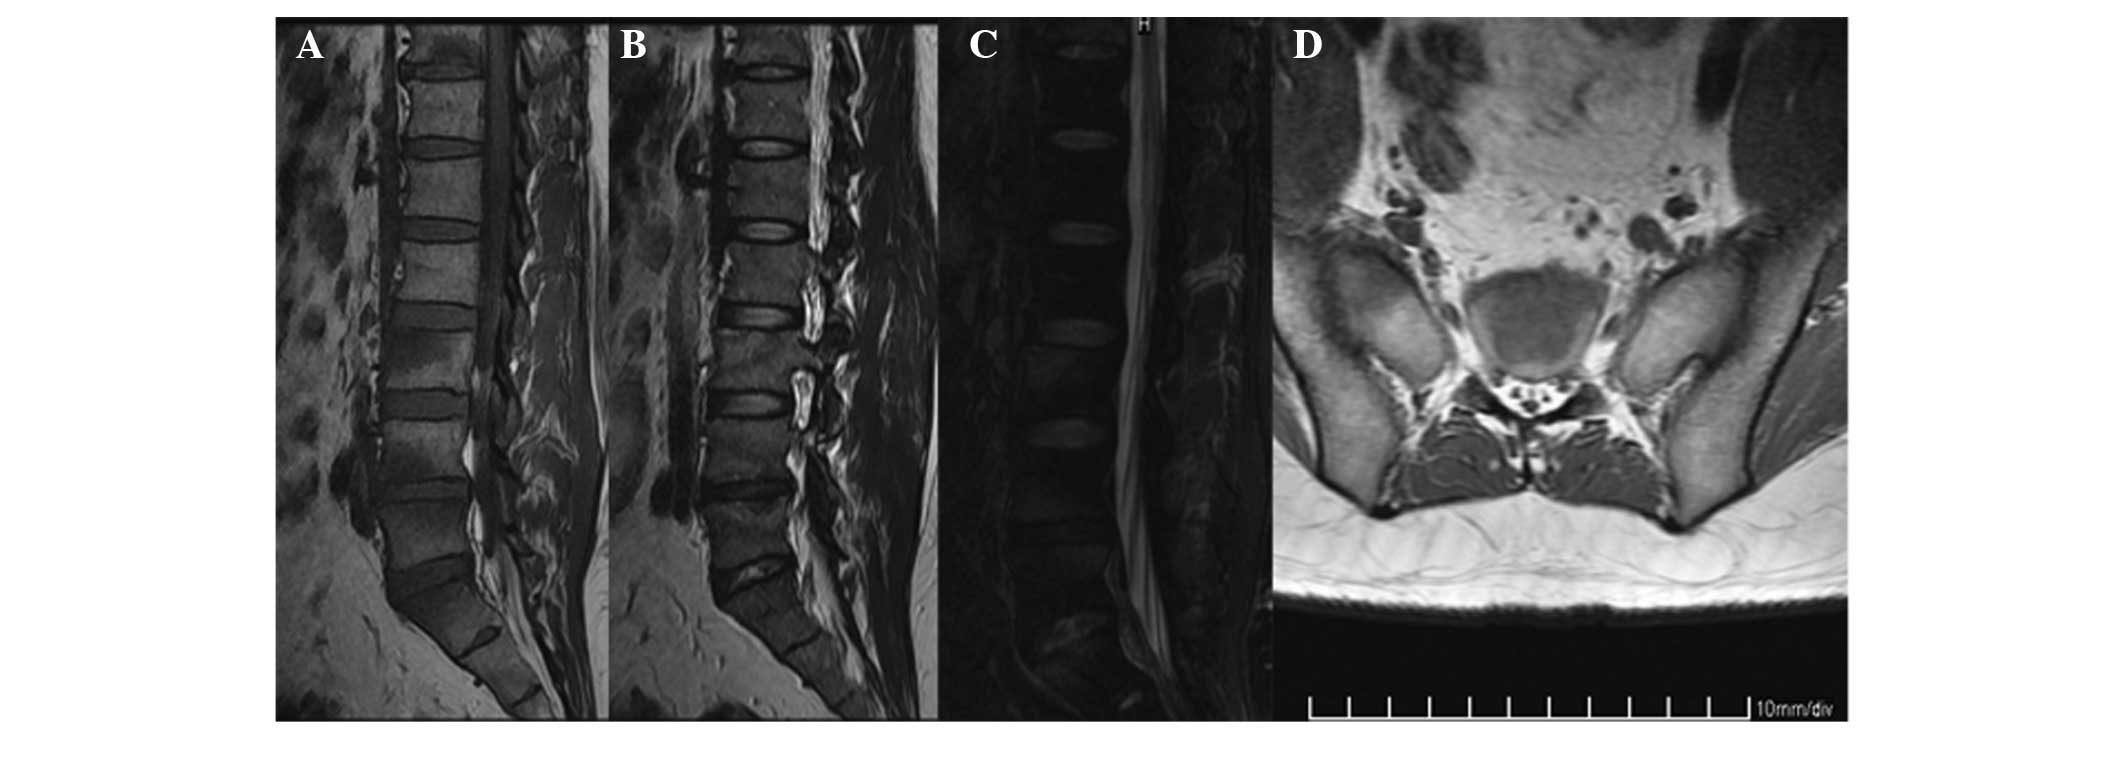

Computerized tomography (CT) scans of the sternum, sternoclavicular joints and sacroiliac joints revealed osseous erosions on the left sternoclavicular joint area, manubrium (Fig. 2) and bilateral sacroiliac joints. Magnetic resonance imaging (MRI) scans of the lumbar spine and sacroiliac joints demonstrated bone marrow edema at the levels of the T11, L3–L5 and S1 vertebra and the bilateral ala of sacrum (Fig. 3). To evaluate the skeleton, a whole body bone scan (WBS) was performed 3 h following the injection of 25 mCi 99mTc-methylene-diphosphonate. Anterior and posterior views of the WBS revealed intense uptake at the proximal end of the left clavicle, manubrium sterni, fifth lumbar vertebra and right sacroiliac joint (Fig. 4).

Sagittal magnetic resonance imaging (MRI) scans of the lumbar spine revealed diffused inflammatory bone changes in the T11, L3–L5 and S1 vertebral bodies that were (A) hypointense on the T1-weighted image, (B) hyperintense on the T2-weighted image and (C) hyperintense on the fat-saturated T2-fast spin-echo sequences. (D) Axial MRI of the sacroiliac joints demonstrated edema around the bilateral ala of the sacrum on the T1-weighted image.

WBSs using 99mTc-methylene-diphosphonate are important for the diagnosis of SAPHO syndrome, particularly for detecting multiple and early bone involvement. Bone scintigraphy is a sensitive imaging modality that is able to identify uptake in characteristic regions when changes in radiography are absent or subtly abnormal (6). The sternoclavicular junction is the most common site of involvement in adults, followed by the spine and sacroiliac joints (7). In the present case study, all the common sites were involved to a certain extent. The radiological results of SAPHO syndrome consist of osteolysis, osteitis, hyperostosis and osteosclerosis (8) Osteolysis is occasionally observed, particularly in the initial stages of the disease (7,9), as is the case in the current study. CT scans provide a detailed depiction of the osteoarticular lesions and are the primary imaging modality of the chest wall, particularly for the sternoclavicular region. MRI scans are recommended in cases of spondylodiscitis in SAPHO syndrome in order to provide a better understanding of the extent of the inflammatory process. This is due to the fact that chronic sclerotic bone lesions exhibit low signal intensity in T1- and T2-weighted images, whereas active lesions appear hypointense on T1- and hyperintense on T2-weighted images (8). MRI results reveal SAPHO vertebral lesions, including body corner erosions, signal abnormalities in the contiguous vertebrae and the narrowing of disk spaces (10).